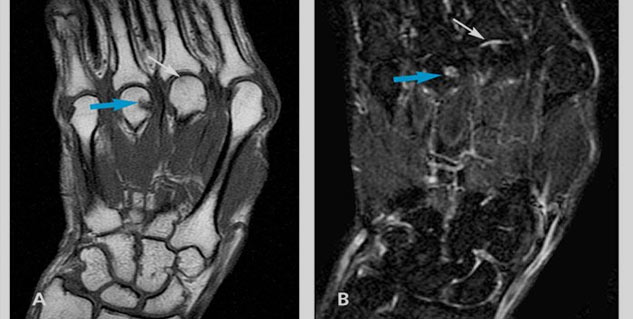

1. एमआरआई और एक्स-रे (MRI and X-ray)

अर्थराइटिस का पता लगाने के लिए डॉक्टर आपको एक्सरे या एमआरआई करवाने की सलाह दे सकते हैं। हालांकि एक्स-रे में लिगामेंट या मसल्स नजर नहीं आती हैं, उसके लिए डॉक्टर एमआरआई करते हैं। एमआरआई की मदद से हड्डी, ज्वॉइंट्स में बदलाव या बीमारी का पता चलता है। अर्थराइटिस का पता लगाने के लिए कुछ आर्गन की बायोप्सी भी की जाती है।